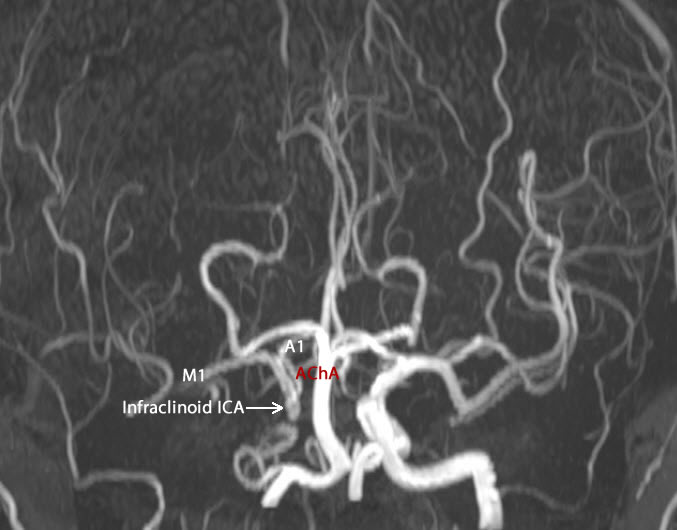

The patient was operated by me 15-January-2015 for complete occlusion of the right ICA for repeated CVA attacks with left sided plegia. The patient came for follow up and MRA of the carotids performed 03-March-2015 showed acceptable circulation of the right ICA with improvement of the patient neurologic status. The patient then came 07-March-2019 telling that he got enlargement under the old incision site pulsating  with pain at the lesion for the last 10 days. The patient was neurologically free. He was sent for investigations. MRA of the carotids showed pseudo-aneurysm with dissection 16.8x7.4 mm at the right ICA with clot 41.5x21.4 mm multilobulated lateral to the artery. The right extracranial ICA is not seen but the cross circulation is filling the right infraclinoid, clinoid, supraclinoid, M1 and A1 from the left side.

Fig:-1. The right ICA receiving cross circulation from the left side.